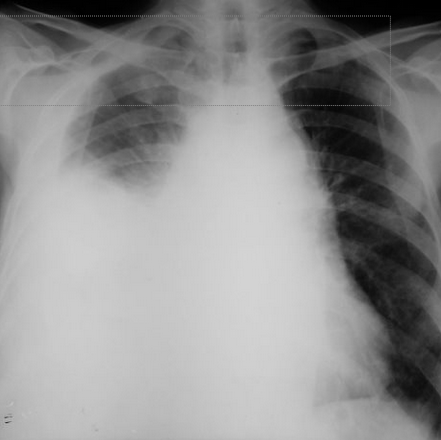

Rx toracică, incidență P-A

DESCRIERE:

la niv. întregului hemitorace stg → opacitate extinsă, nesistematizată, de intensitate mare, omogenă

caracter retractil → tracționează traheea și mediastinul de partea afectată

fără bronhogramă aerică

duce la micșorarea spațiilor intercostale

la niv. hemitoracelui controlateral → hipertransparență compensatorie

DX: atelectazie prin NBP central endobronșic (pe bronhia principală stg)

DD: pleurezie masivă → caracter expansiv